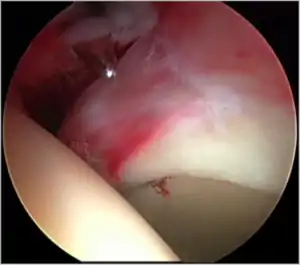

Figure 8.Cartilage delamination. A small area of acetabular cartilage has lifted from the underlying bone, being demonstrated by use of the arthroscopic probe

Cam impingement is created by the abnormal development of the femoral head-neck junction causing what has previously been described as a 'pistol-grip deformity'. This type of deformity is characterised by varying amounts of abnormal bone on the anterior and superior femoral neck at the head-neck junction (see fig. 6). The head-neck junction is at the base of the ball of the hip, where it joins the short neck, which in turn carries on downwards into the femur, or thighbone, itself. A bony protrusion or bump at the head-neck junction has been likened to a cam, an eccentric part of a rotating device. This leads to joint damage as a result of the non-spherical femoral head being forced into the acetabulum mainly with flexion and/or internal rotation. This may impart compression and shear forces to the articular cartilage, and may lead to labral tears and peeling away of the articular cartilage from the underlying bone, so-called cartilage delamination (see fig. 8).[9][10]